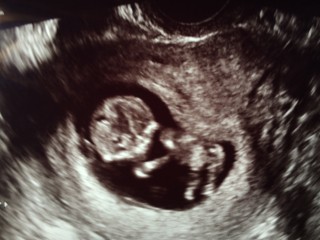

エコーではかわいく動いていました!顔も目鼻口分かるようになりだんだん人間らしくなってきて愛しさ倍増です。あと毎日エンジェルサウンドで心拍聞いています。つわりは相変わらず続行中。